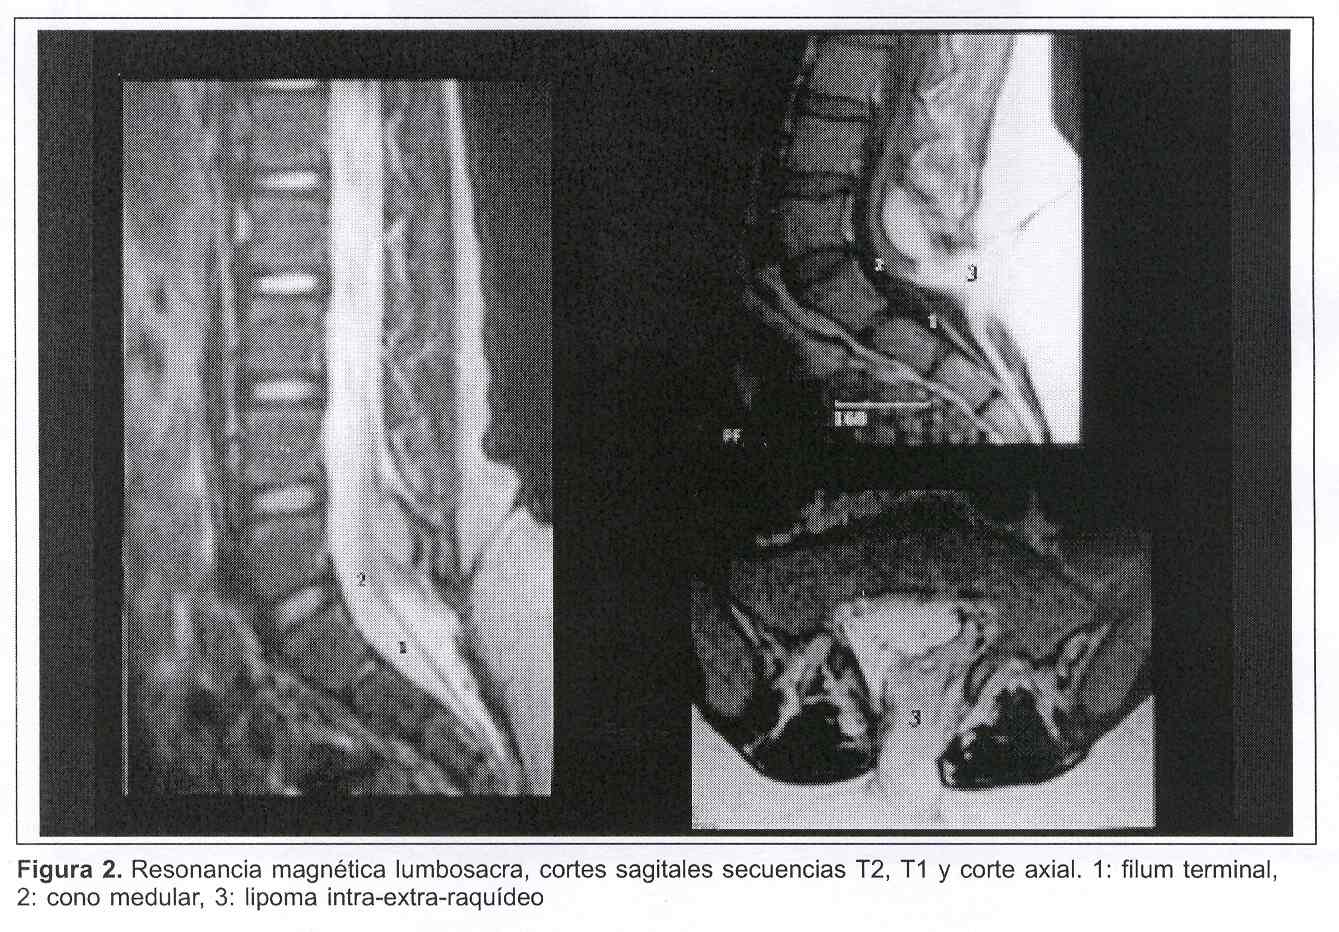

La resonancia magnética lumbosacra muestra, por un lado, la malformación lipomatosa ingresando al raquis lumbosacro por el defecto óseo; por otro lado, se aprecia una médula baja con el cono a nivel de L5-S1 y un filum terminal engrosado (figura 2).

Figura 1. A y B: pie en equinovaro. C y D: lipoma lumbosacro con angioma dérmicoFigura 2. Resonancia magnética lumbosacra, cortes sagitales secuencias T2, T1 y corte axial. 1: filum terminal, 2: cono medular, 3: lipoma intra-extra-raquídeo